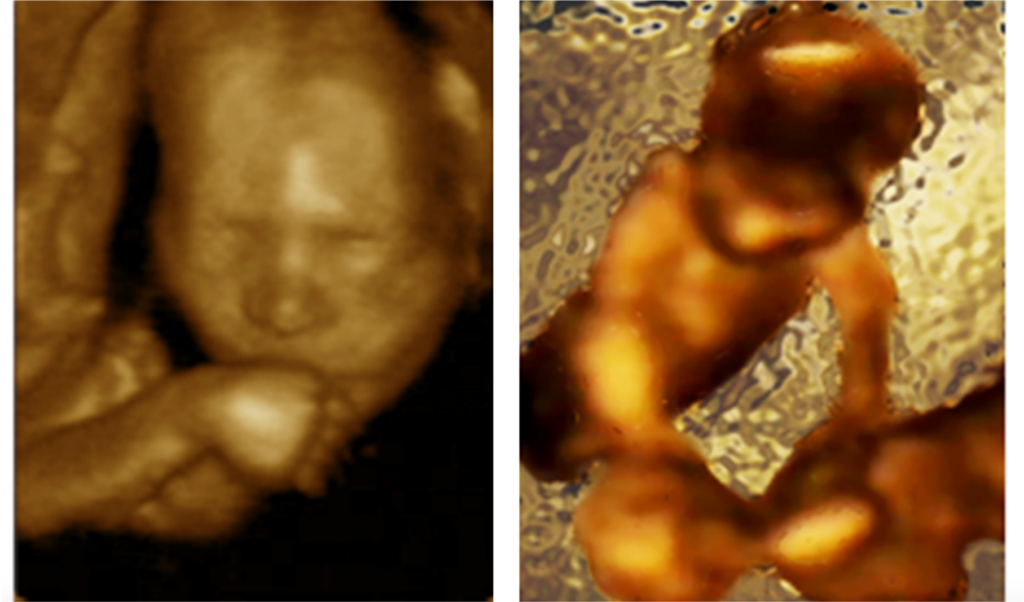

Left: self-directed movement towards the mouth Right: the foetus "caressing" the head of the sibling.

Newborns come into the world wired to socially interact. Is a propensity to socially oriented action already present before birth? Twin pregnancies provide a unique opportunity to investigate the social pre-wiring hypothesis. Although various types of inter-twins contact have been demonstrated starting from the 11th week of gestation, no study has so far investigated the critical question whether intra-pair contact is the result of motor planning rather then the accidental outcome of spatial proximity. ...Kinematic profiles of movements in five pairs of twin foetuses were studied by using four-dimensional ultrasonography during two separate recording sessions carried out at the 14th and 18th week of gestation. We demonstrate that by the 14th week of gestation twin foetuses do not only display movements directed towards the uterine wall and self-directed movements, but also movements specifically aimed at the co-twin, the proportion of which increases between the 14thand 18th gestational week. ...We conclude that performance of movements towards the co-twin is not accidental: already starting from the 14th week of gestation twin foetuses execute movements specifically aimed at the co-twin.